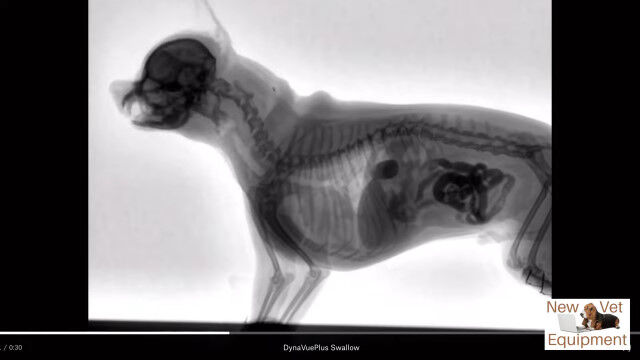

動物用レントゲンシステム、ダイナビューを用いて撮影された、犬がエサを食べる最中の体内の様子。

口から食道を通り、ゆっくり胃袋へ流れ込む様子が動画ではっきり確認できる。

Youtubeの概要欄に記載がなくて分からなかったけど、これ犬種はなんだろうね。

Veterinary Fluoroscopy - Watch the Swallow!